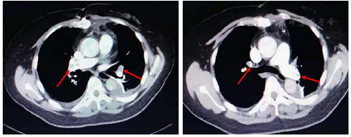

CTPA提示主肺动脉显影良好,未见腔内充盈缺损,左、右肺动脉主干远端可见多发不规则腔内充盈缺损。左上肺动脉前支、尖后支管腔内可见低密度充盈缺损,远段分支显影不良。左舌段肺动脉上、下支分叉处管腔内可见低密度充盈缺损,远段显示良好,左下肺动脉近段及其分支内前基底支管腔内可见低密度充盈缺损,远段分支显影尚可,外后、背基底支显示良好;右上肺动脉及其分支前、尖、后支管腔内可见低密度充盈缺损,远段分支显影欠佳。右肺中叶段及其分支内、外支管腔内可见低密度充盈缺损,远段分支显影尚可。右下肺动脉及其分支内、前、外、后、背基底支管腔内可见低密度充盈缺损,远段分支显影不良。双侧胸腔积液,左下肺膨胀不良(图2)。